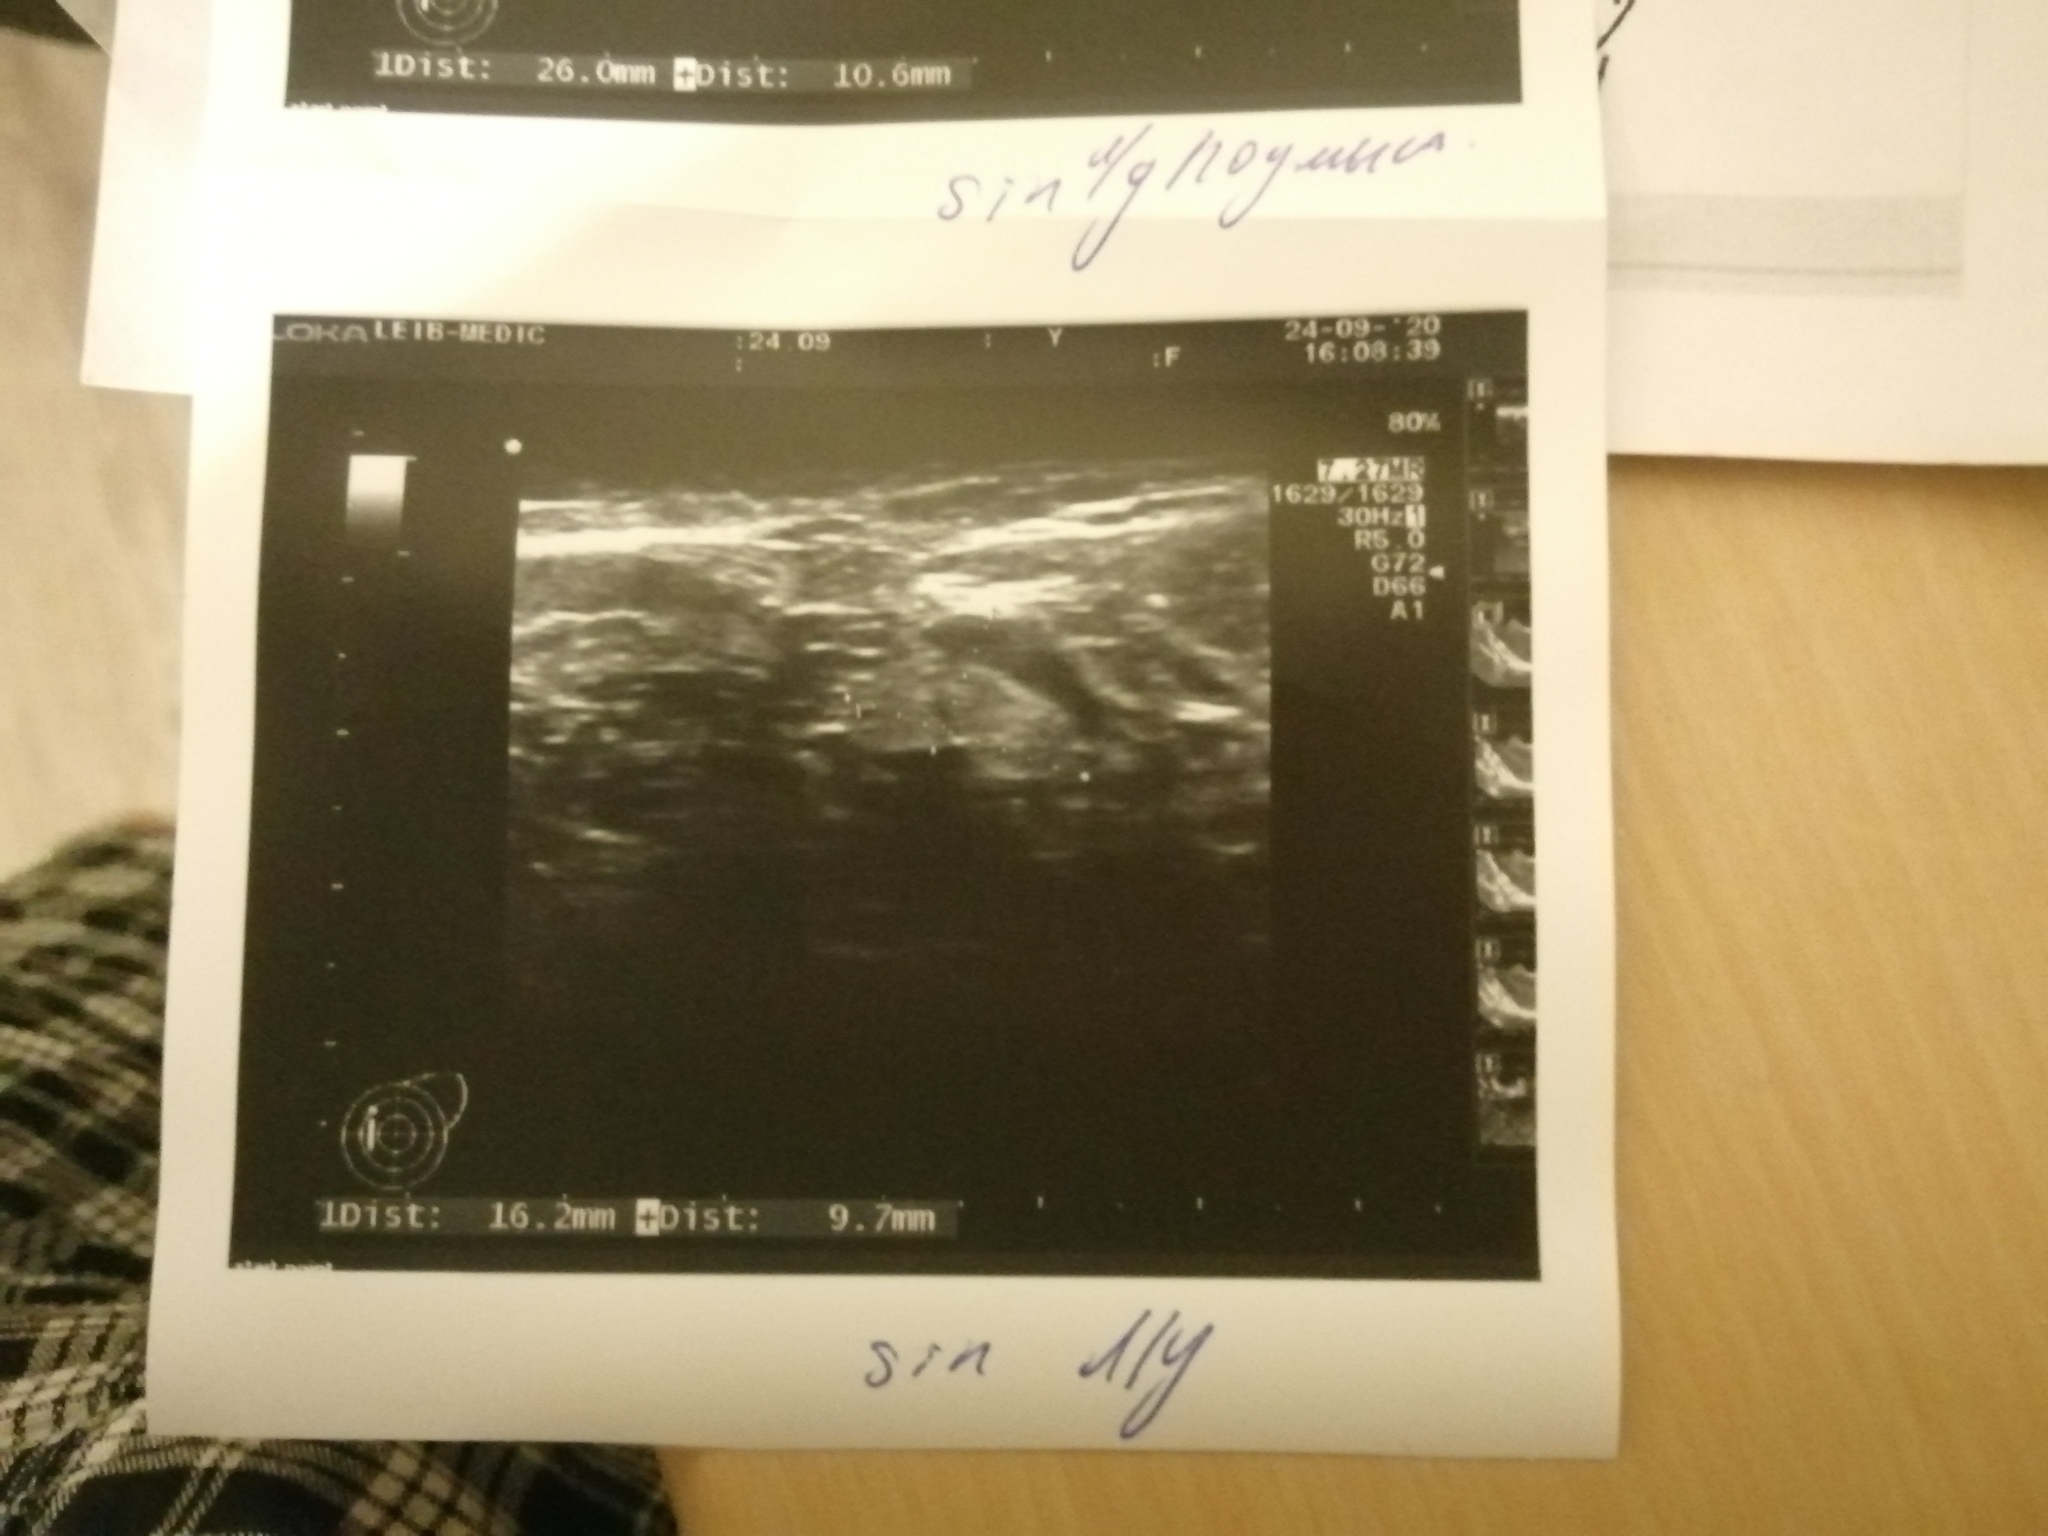

Пол года назад умерла тёща от рака молочной железы. Недавно с супругой ездили на дальняк (1000 км туда-обратно), она была за рулем. После долгой дороги у неё заболела подмышка. Прошло 3 месяца после этой поездки, боль не прошла. Сходила на УЗИ, нашли вроде как уплотнение в груди. Сказали ехать к мамологу. Супруга после этого УЗИ ходит сама не своя и плачет постоянно. Ничего не говорит. Я конечно грешу на то, что после смерти её мамы она в стрессе и все такое. Пока она в душ ходила, сфоткал документы из больницы. Будут во вложении. Подскажите пожалуйста, что это такое и чего ждать и на что это похоже, потому, что она молчит и на мои вопросы не отвечает. Заранее всем спасибо!